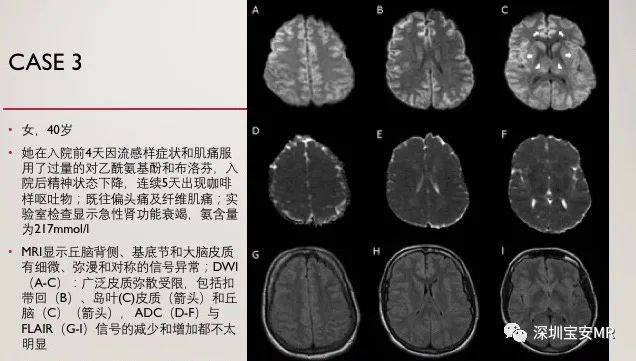

以上三个病例的特点:临床血氨明显升高,MRI双侧岛叶、扣带回皮层及丘脑异常信号,DWI呈高信号。诊断:急性高氨血症脑病。

3个病人都有急性氨水平升高。尽管在急性肝功能衰竭中,血氨浓度升高是常见的,但其他后天病因包括药物(如丙戊酸、巴比妥类、麻醉剂、酒精和化疗)、胃肠道感染、肾脏疾病、尿素产生机体的尿路感染、输尿管乙状结肠造口术、肠外营养、雷氏综合症、骨髓移植、实体器官移植、严重的肌肉劳损和感染性休克。原发性病因如代谢异常,也可引起急性高氨血症脑病。

目前还不清楚为什么岛叶和扣带皮质特别容易受到氨的毒性影响。氨通过被动扩散和阳离子通道穿过血脑屏障。它影响多种神经递质,特别是兴奋性谷氨酸能NMDA受体和GABA受体的调节。最终,神经元凋亡发生。高氨血症单独出现足以引起体内脑水肿和体外星形胶质细胞肿胀,通过增加脑血容量增加颅内压。

尽管所有3例患者的氨水平均急性升高,且无持续缺氧的记录,但磁共振成像结果导致缺氧缺血性脑病的误诊。所有3例患者的T2高信号和弥散受限与后者(缺氧缺血性脑病)相似。所有3名患者在神经系统检查最差的时候氨含量都很高。累及的区域包括弥漫性皮质,特别是岛叶皮质和扣带回皮质以及基底节的深部灰质。

在高氨血症的临床背景下,双侧对称性的岛叶和扣带回皮质受累以及双侧丘脑受累的模式,在MRI上主要表现为弥散受限,应提醒临床医生注意高氨血症脑病的可能性,尤其是在没有缺氧缺血性事件的情况下。